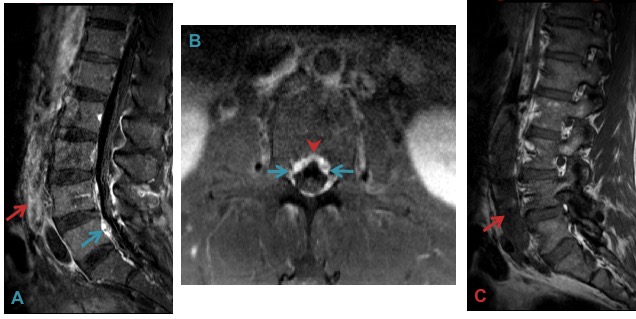

Backpressure from IVC thrombosis (A & C) causes congestion of the epidural venous plexus (A & B). Clue to the diagnosis is enhancement on each side of the midline septum (arrowhead).